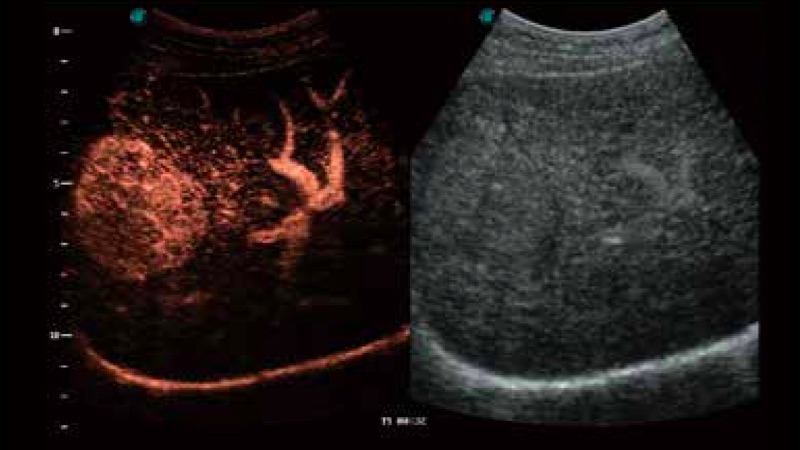

造影成像

造影成像功能和定量分析工具包使医生能够更好的评估血流灌注情况。独特的动态声压控技术有效控制造影剂的声压,保证更长的造影剂持续时间,更好的观察病变灌注的延迟相位。

S-Live 高分辨率容积成像

通过仿真成像技术对3D/4D立体数据进行渲染,多种初始光源位置可选,并支持轨迹球360°光源位置自由调节,清晰显示不同方位容积图像细节。